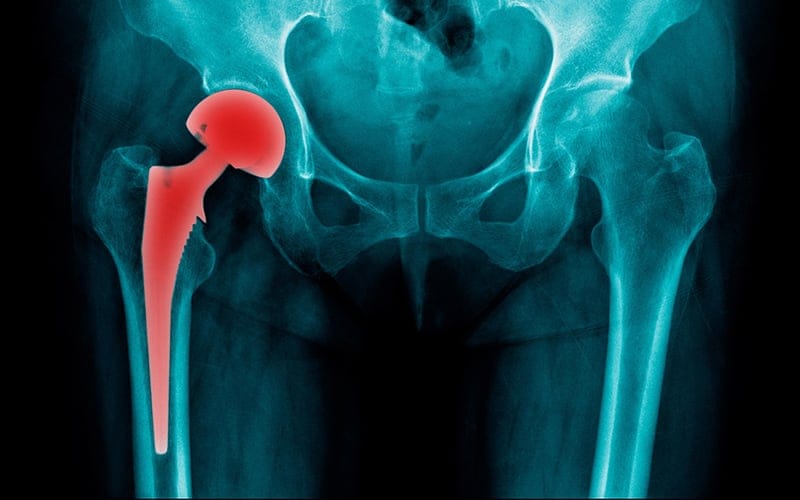

تأثيره على العظام والمفاصل

استمرار الالتهاب دون علاج قد يسبب:

- تآكل غضروف مفصل الحوض

- خشونة مبكرة

- تيبّس وصعوبة في الحركة

- تغير نمط المشي

- تحميل زائد على الركبتين والعمود الفقري